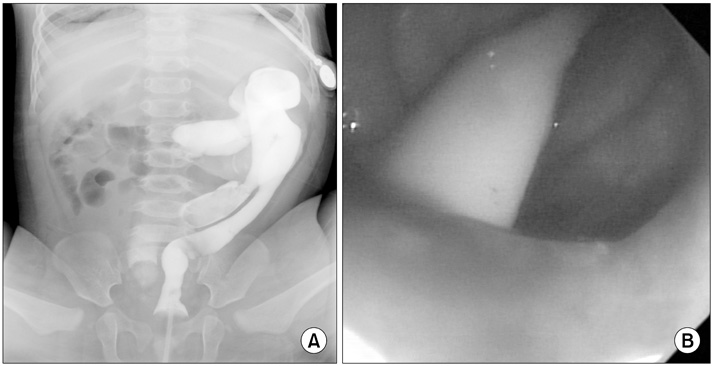

Fig. 1). Under general anesthesia, a small opening located posterior to and near the vagina at vestibule was found. The structure that had been misdiagnosed as a fistula based on the colon study was not present. The patient had a normally sited anus, an anterior ectopic anus, and a double vagina (

Fig. 2). A catheter was inserted through the ectopic anus, and an intraoperative contrast study and sigmoidoscopy were performed. A parallel tubular duplication with a common wall was found. The common wall extended 5 cm from the anal verge to the sigmoid colon and then 20 cm to the level of the proximal sigmoid colon. Proximally, the anterior duplication and normal colon merged and formed a normal colon. Because most of the stool moved through the anterior duplication and because the diameter of the anterior duplication was larger than that of the normally located colon (

Fig. 3), complete resection of both the anterior duplicated bowel and posterior native bowel up to the merging point with colo-anal anastomosis was performed (

Fig. 2Examination under general anesthesia revealed a normal anus, an anterior anorectal duplication (catheter-inserted state), and duplicate vaginal openings.

Fig. 3Intraoperative findings. (A) The intraoperative contrast study revealed that the contrast injected via the anterior anorectal duplication filled the normal colon and rectum and that there was a connection between the duplication and the normal colon at the level of the proximal sigmoid colon. (B) Intraoperative sigmoidoscopy at the merging point revealed that a catheter inserted via the anterior anorectal duplication could be observed by a scope inserted via the normal anus.